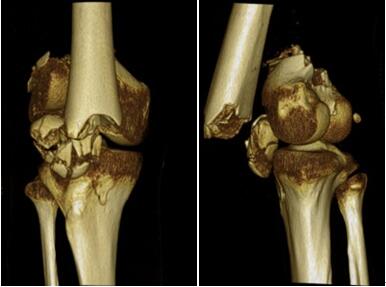

好在命大,小涛挺过了病危期,家人见到还有一丝希望,就安排小涛转院到了广东三九脑科医院。初入院的小涛,依然是个植物人,合并身体多处损伤。由于坠楼后,小涛先是双脚着落,然后顺势俯卧倒地,因此他不仅颅脑损伤严重,而且双腿及面部还有多处骨折。病情诊断:一、右股骨髁上髁间粉碎性骨折,二、右髌骨粉碎性骨折,三、左胫骨骨折,四、左跟骨开放性粉碎性骨折并伤口感染,五、右足部骨折,六、左足舟距关节脱位;七、右足跗骨多发骨折伴脱位;八、重型颅脑损伤:颅底骨折;弥漫性轴索损伤?;颌面部多发骨折;九、双肺挫伤并感染;十、躁狂症。”

做好术前准备后,王延斌主任及其团队在全麻下为小涛实施“右股骨髁上髁间骨折切开复位内固定术+左跟骨清创负压吸引术”。由于骨折部位结构复杂,粉碎严重,手术难度大。手术从晚上7点到次日的凌晨3点多,手术时间持续约八个小时,顺利完成。

▲术前